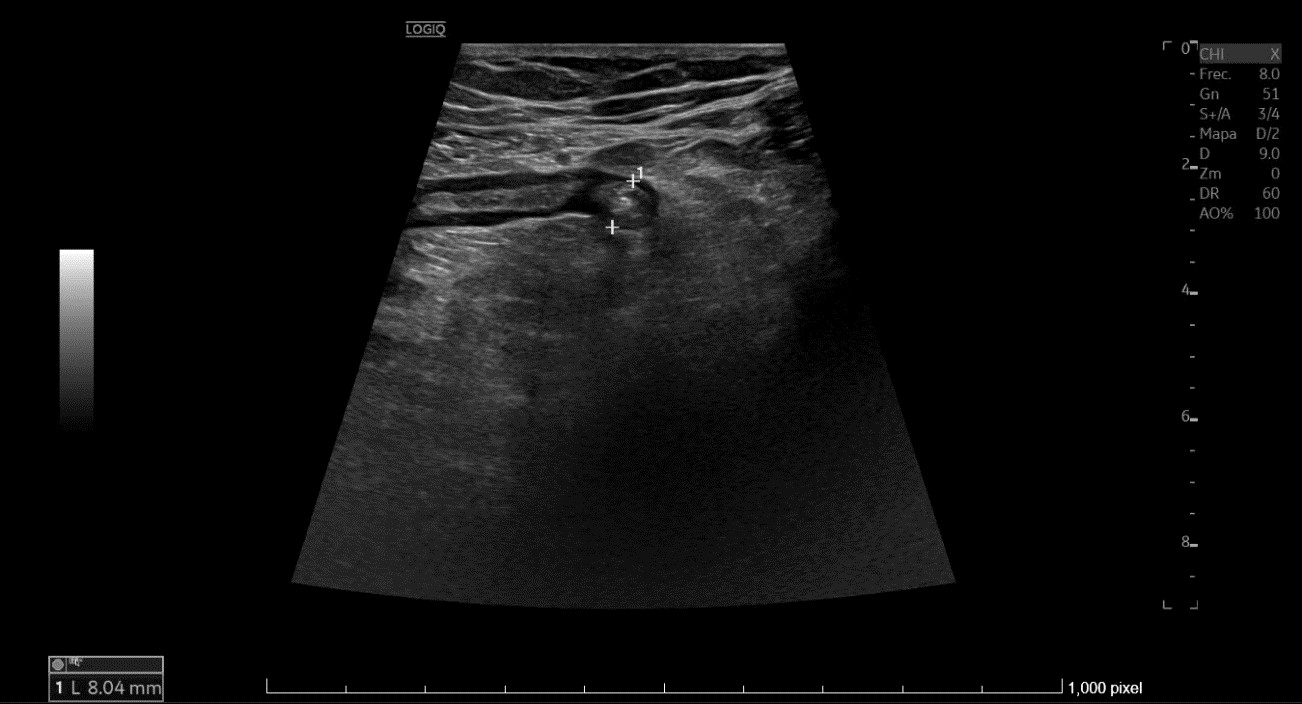

• En urgencias, de inicio se realiza radiografía abdominal sin datos de obstrucción intestinal. Ante persistencia de dolor intenso, leucocitosis y aumento de PCR en analítica, se repite la ecografía (utilizando también sonda lineal) con hallazgo de diverticulitis aguda sigmoidea con datos de peritonitis regional pélvica, y posteriormente se realiza un TC abdominal con conclusión de diverticulitis aguda con pequeños abscesos murales, perforación de un divertículo y peritonitis pélvica.

La ecografía puede ser la exploración inicial en pacientes con sospecha de diverticulitis aguda. Además, la utilización de sonda lineal en zonas superficiales del abdomen, puede dar mayor información que solamente la convexa. Al disponer de ecografía en consulta y observar los hallazgos sospechosos de posible afectación de sigma, se facilitó la toma de decisiones y ayudó a no retrasar el diagnóstico, reafirmando la necesidad de derivación a valoración en urgencias.